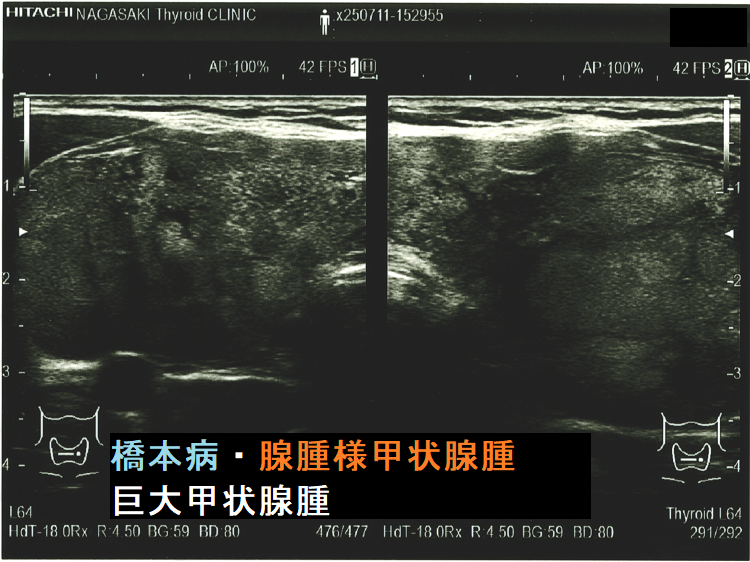

ケース⑤ 橋本病を基盤とする腺腫様甲状腺腫・巨大甲状腺腫(気管・食道圧排)